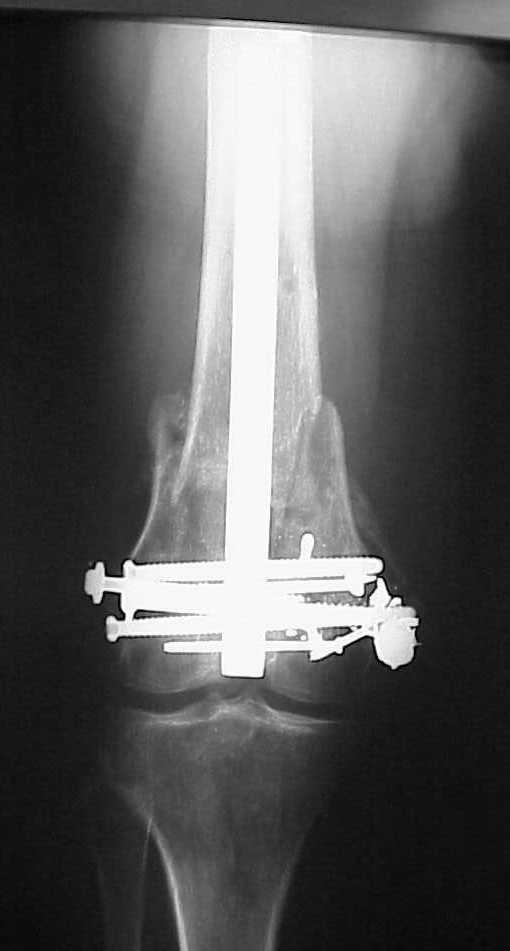

place one anterior to where IMN will go if anterior cortex if insufficient and AP screws on either side of the IMN out of the trochlea to provide some additional varus/valgus stability. I worry about the leg going into valgus w/the lack of lateral cortex.

See attached case that was done several years ago before LISS. He had comminuted trochlea and anterior blocking screws were used to prevent anterior IMN cut-out.